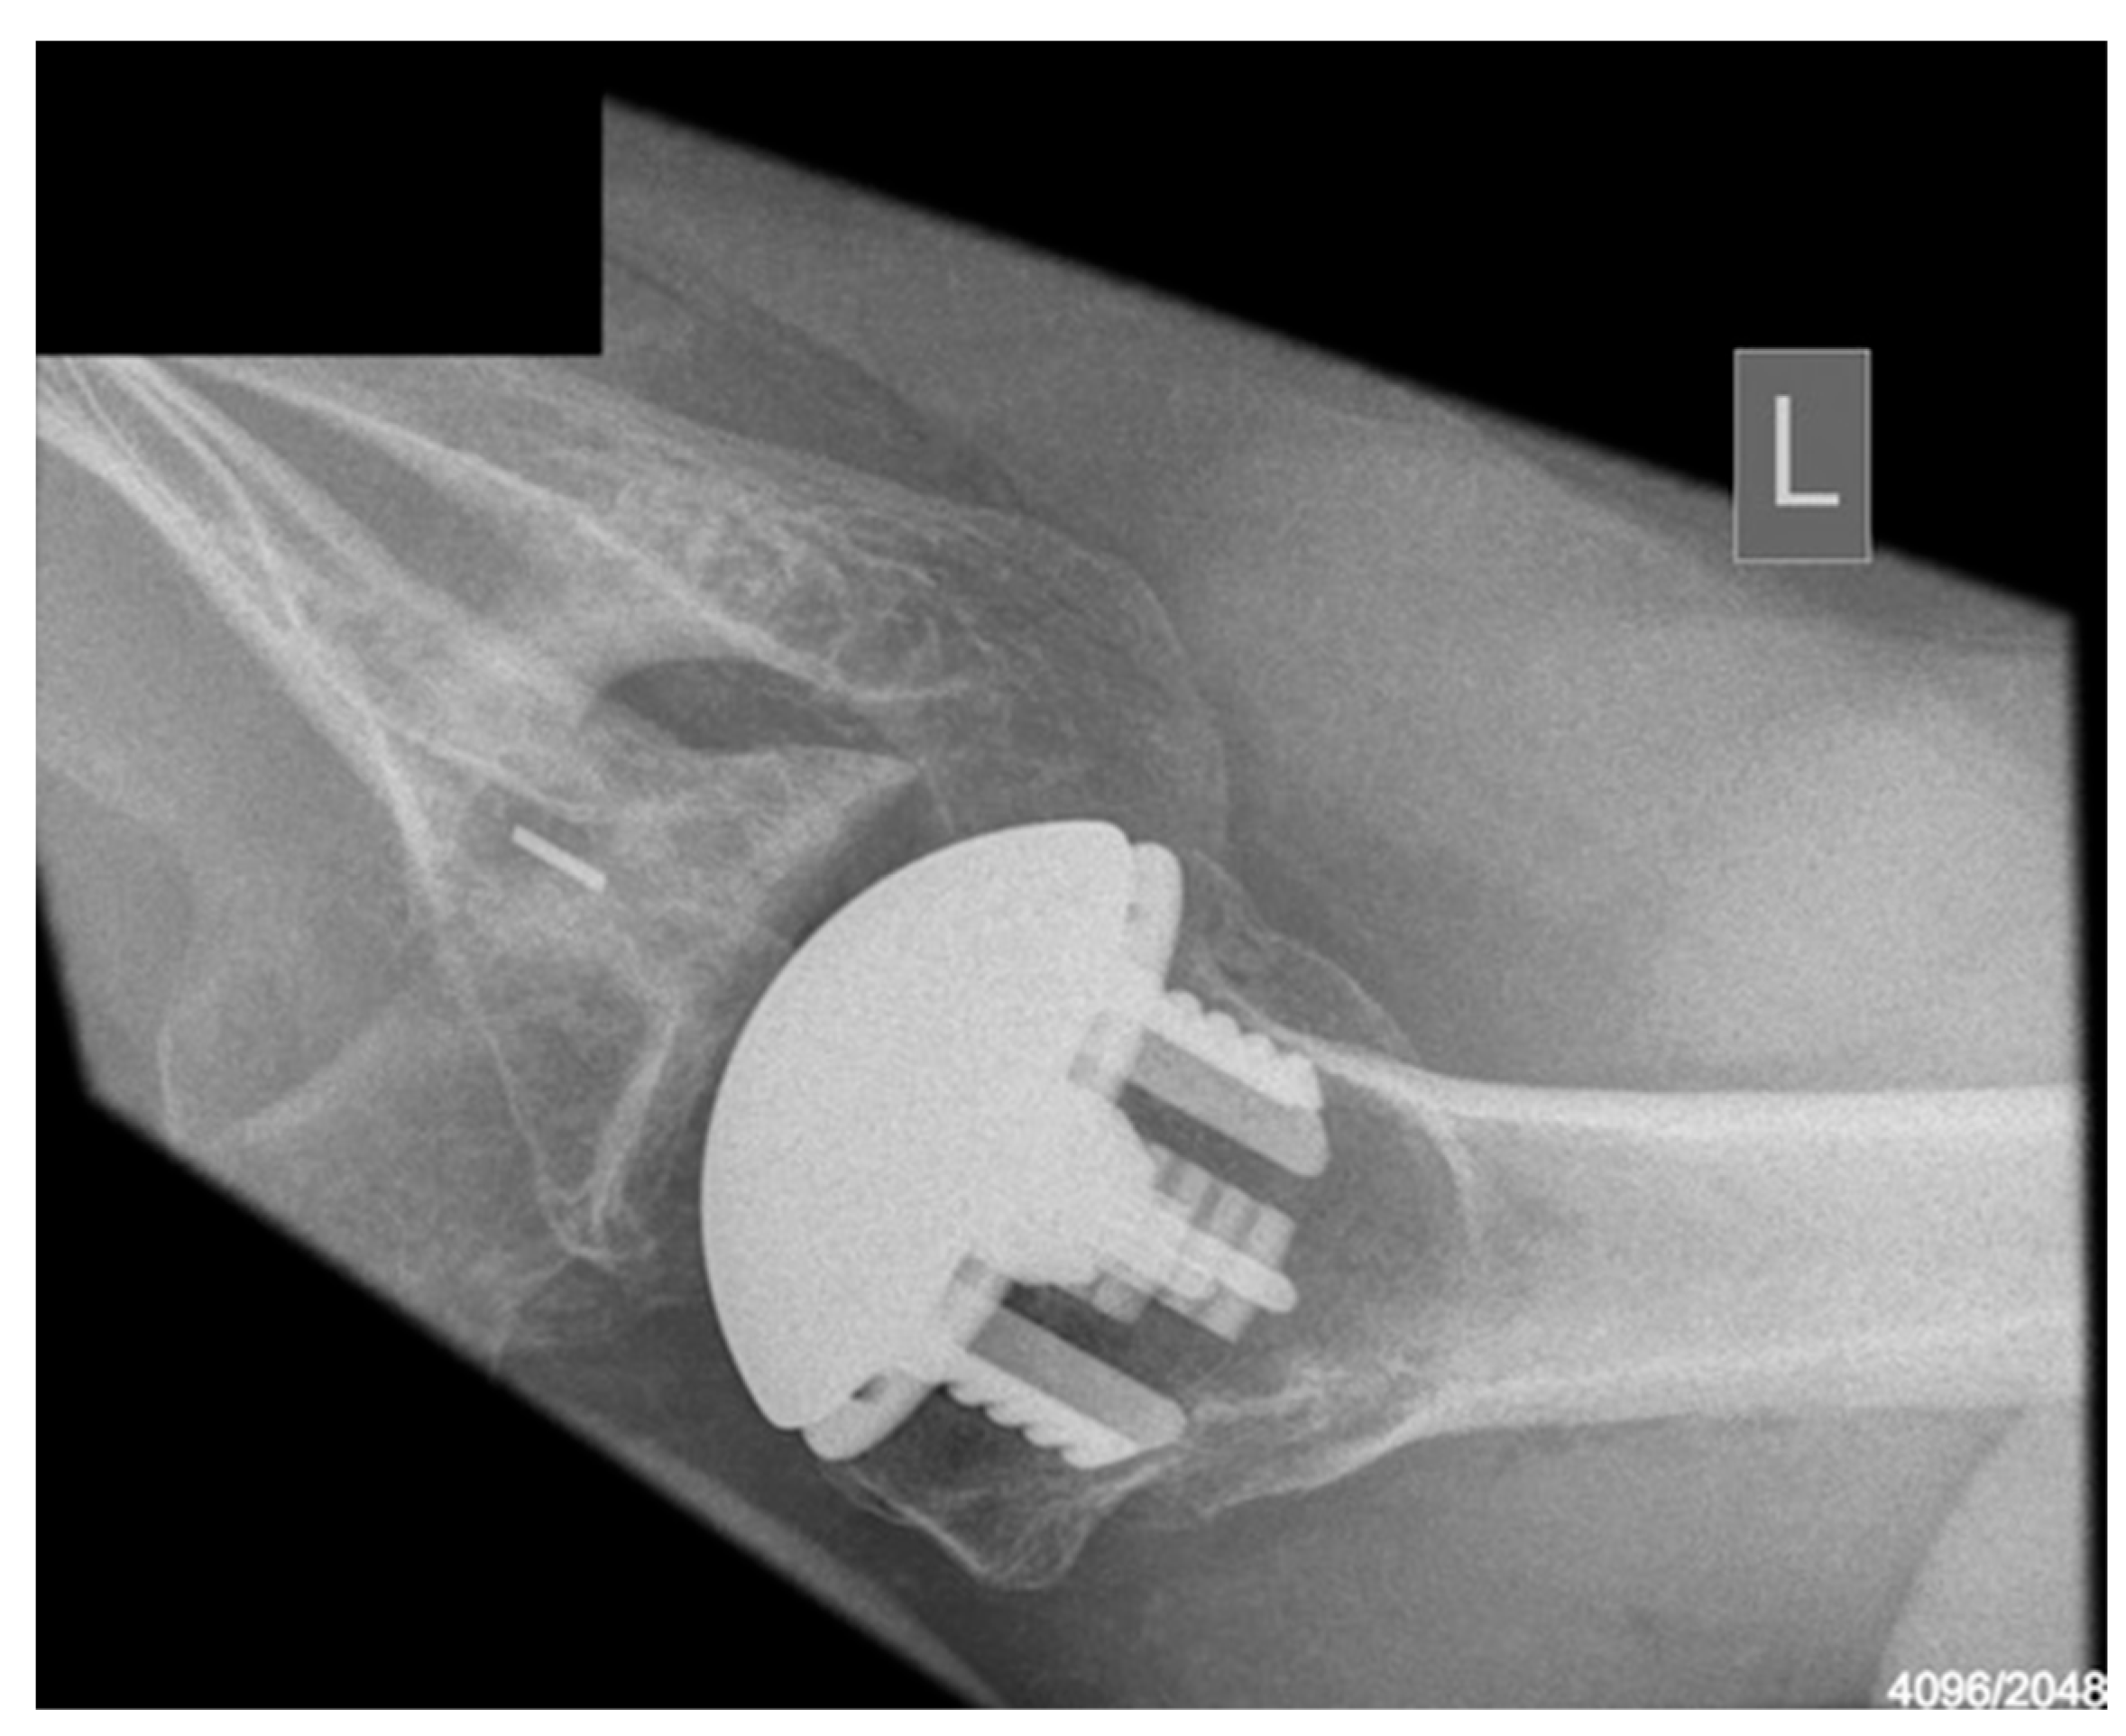

Medium-Term Clinical Outcomes of the Global Icon Stemless Shoulder System: Results of a 2-Year Follow-Up

2. Materials and Methods

3.2.2. Radiological Outcomes